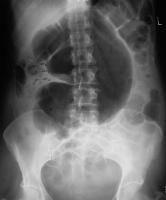

A simple abdominal radiograph is diagnostic of acute sigmoid volvulus in 57% to 90% of cases, presenting with the classic “coffee bean sign.”49,50 (See Figure 3.) These patients will display a dilated sigmoid colon and also may display multiple air-fluid levels within the large and small bowels.42 CT imaging also may be used, with a typical “whirl pattern” in the colon indicating the presence of sigmoid volvulus. (See Figure 4.) CT scans have been reported to be diagnostic in nearly 100% of cases.42

Figure 3. Abdominal X-Ray Demonstrating Coffee Bean Appearance Consistent with Sigmoid Volvulus |

Source: Image courtesy of J. Stephan Stapczynski, MD. |